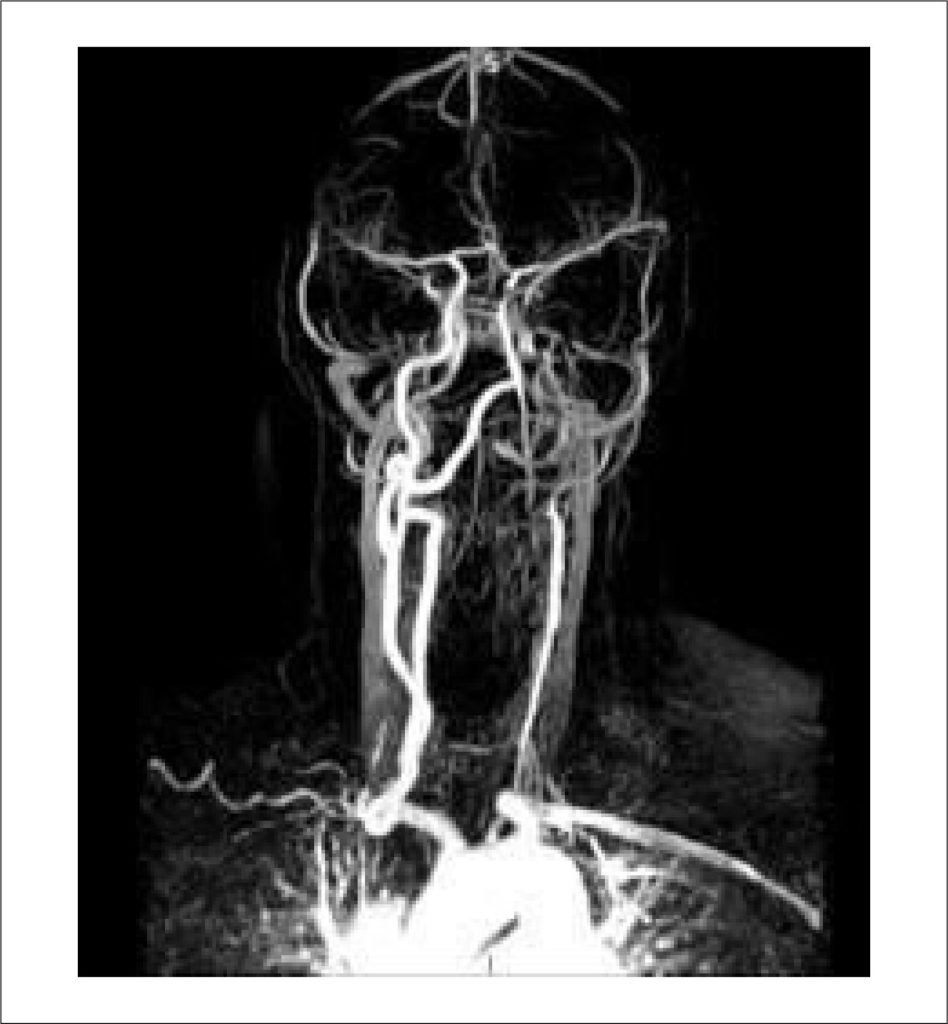

A arterite de Takayasu (AT) é uma vasculite rara de grandes vasos que acomete principalmente a aorta e seus principais ramos e afeta predominantemente mulheres em idade reprodutiva. Relatamos o caso de uma mulher que apresentou um acidente vascular encefálico (AVE) isquêmico aos 20 anos e um ataque isquêmico transitório aos 53 anos, com diagnóstico de AT realizado apenas após o segundo evento cerebrovascular. Embora o AVE isquêmico seja uma manifestação inicial incomum da AT, o reconhecimento precoce e o manejo oportuno são essenciais para prevenir novas complicações e melhorar os desfechos a longo prazo.